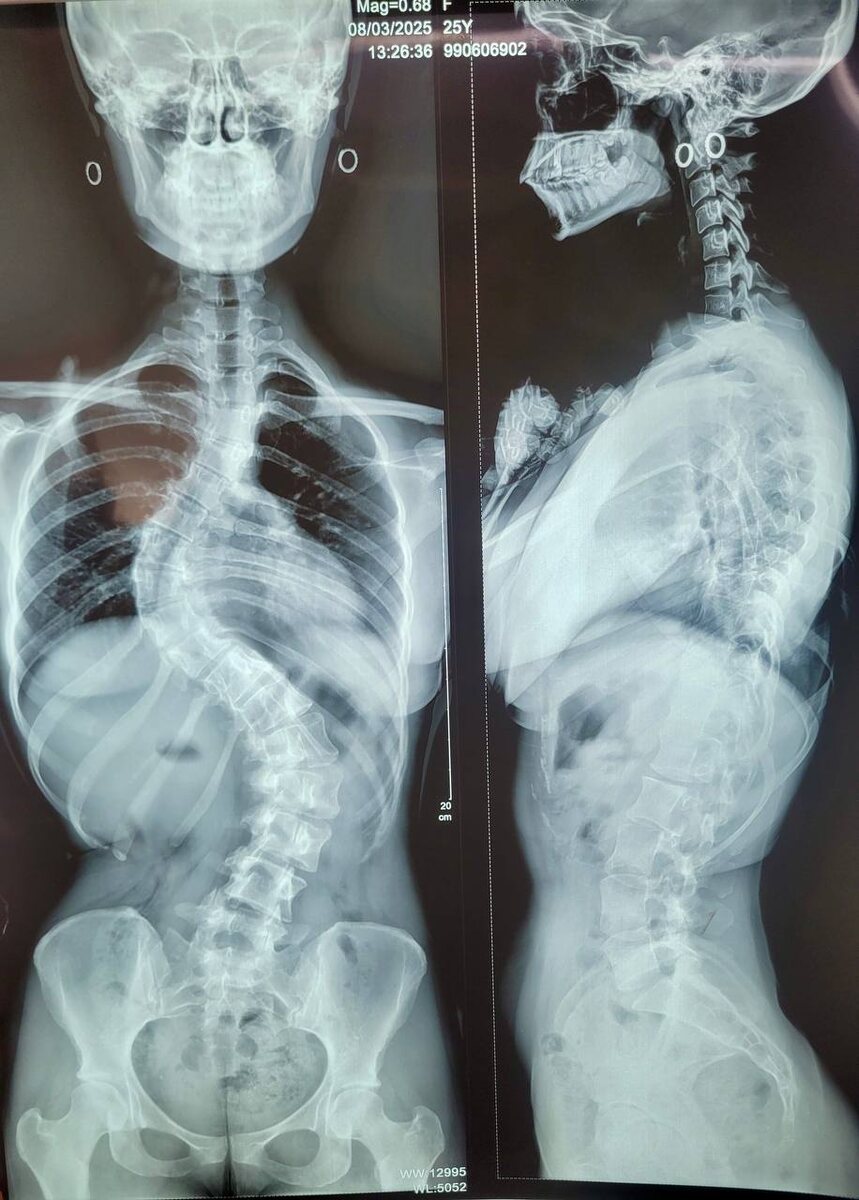

На первом этапе операции 25-летней пациентке исправили сколиоз позвоночника 4 степени в Университетском клиническом центре им. В.В. Виноградова (филиал) РУДН.

Команда специалистов вместе с врачом – травматологом-ортопедом Антоном Владимировичем Шайкевичем провели первый этап динамической коррекции сколиоза с мгновенным результатом и минимальной кровопотерей.

🔗Пациентка страдала комбинированным сколиозом с детства. Беспокоит косметический дефект в виде реберного горба, болевой синдром, снижение толерантности к нагрузкам.

Первым этапом выполнена вентральная динамическая коррекция грудного отдела позвоночника🔗, - прокомментировал Антон Шайкевич.

В тела позвонков установили специальные винты, через головки которых по большой кривизне сколиотической дуги натянули специальный шнур-корд. Натяжением корда расправляется дуга позвоночника. В отличие от классической статической фиксации позвоночник сохраняет мобильность, пациент может двигаться, наклоняться и поворачиваться. Легче и послеоперационный период, так как сокращается время операции и значительно снижается кровопотеря.

🔗Пациентка начала ходить по палате через сутки после операции, а выходить на улицу - на четвертый день. Через неделю выписалась домой. Ожидаем окончание реабилитации через 6-8 недель для проведения второго этапа операции, чтобы исправить искривление грудного отдела и устранить небольшой горб 🔗, - прокомментировал Антон Шайкевич.